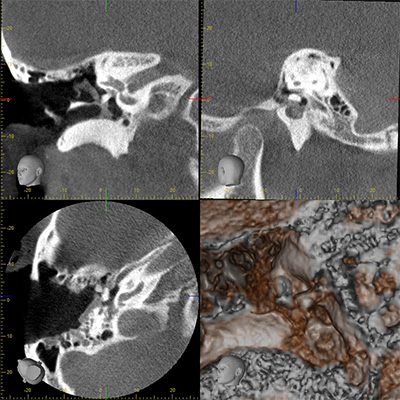

Portable iCT scanner

CT images of an eardrum during tympanoplasty